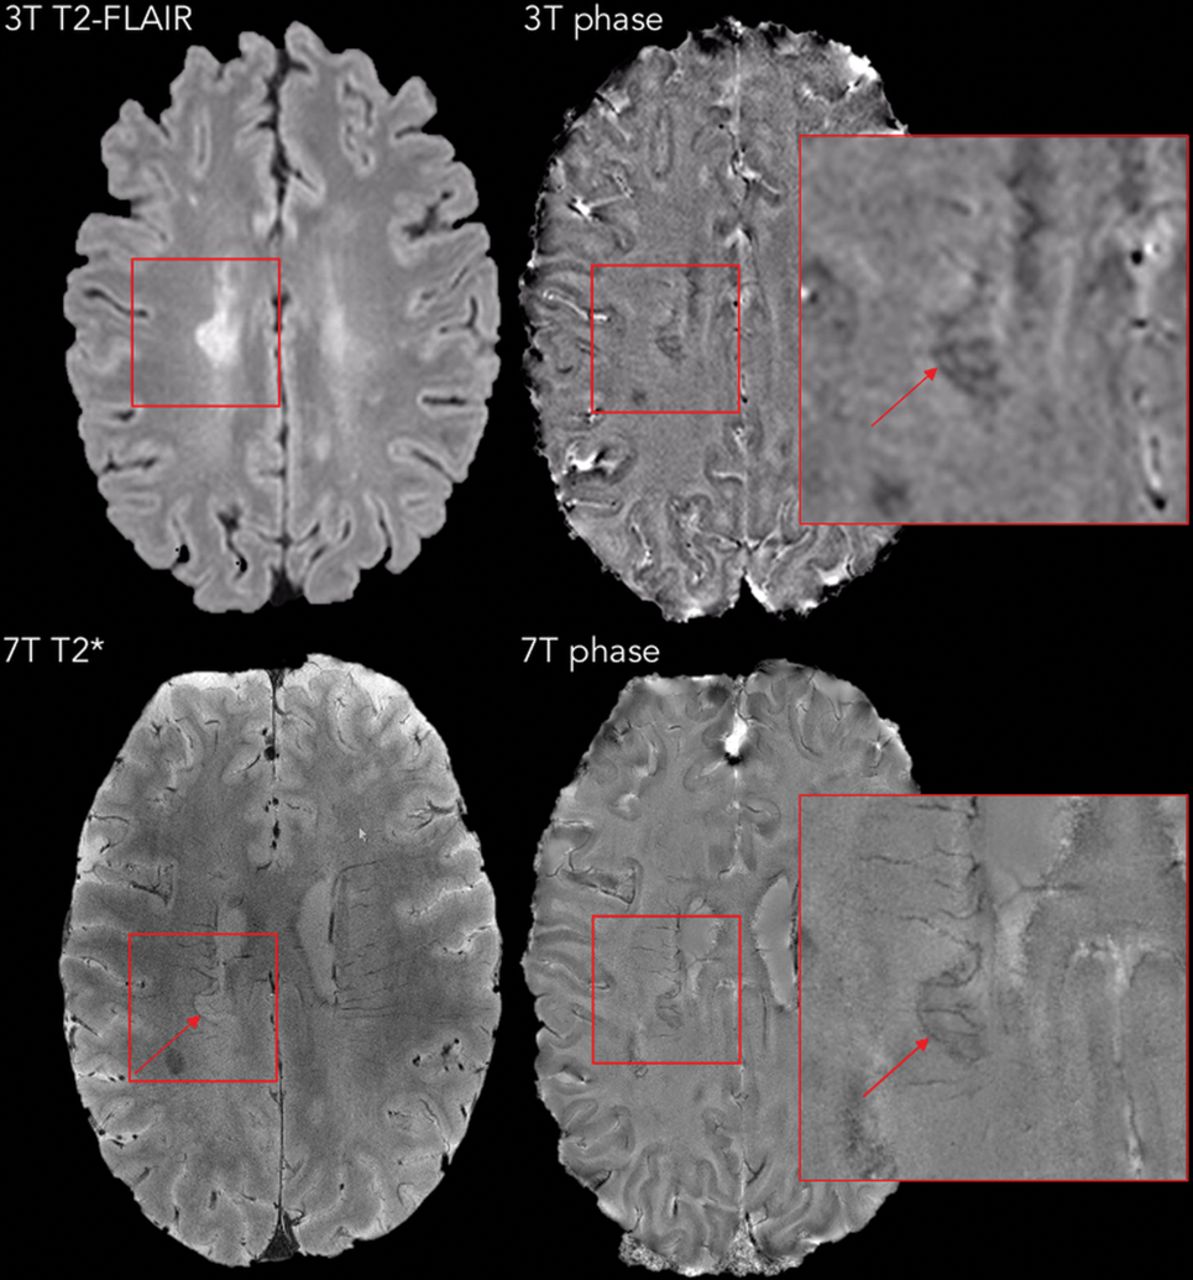

Representative concordant and discordant cases are shown in Figs 1⇓–3.

Representative examples of MS lesions in which a paramagnetic rim (red arrows) can be easily seen on both 7T and 3T phase images. Note the superior image quality at 7T in at least 3 of the 4 examples.

A left centrum semiovale lesion in a 30-year-old woman with relapsing-remitting MS; the time lapse between 3T and 7T scans was 6 months. In this case, the lesion was judged to have a rim on 3T (red arrows), but not on 7T phase images. The false-positive rim at 3T is related to the configuration of blood vessels at the lesion edge. On the other hand, the central vein of the lesion is prominent in both phase images (white arrows).